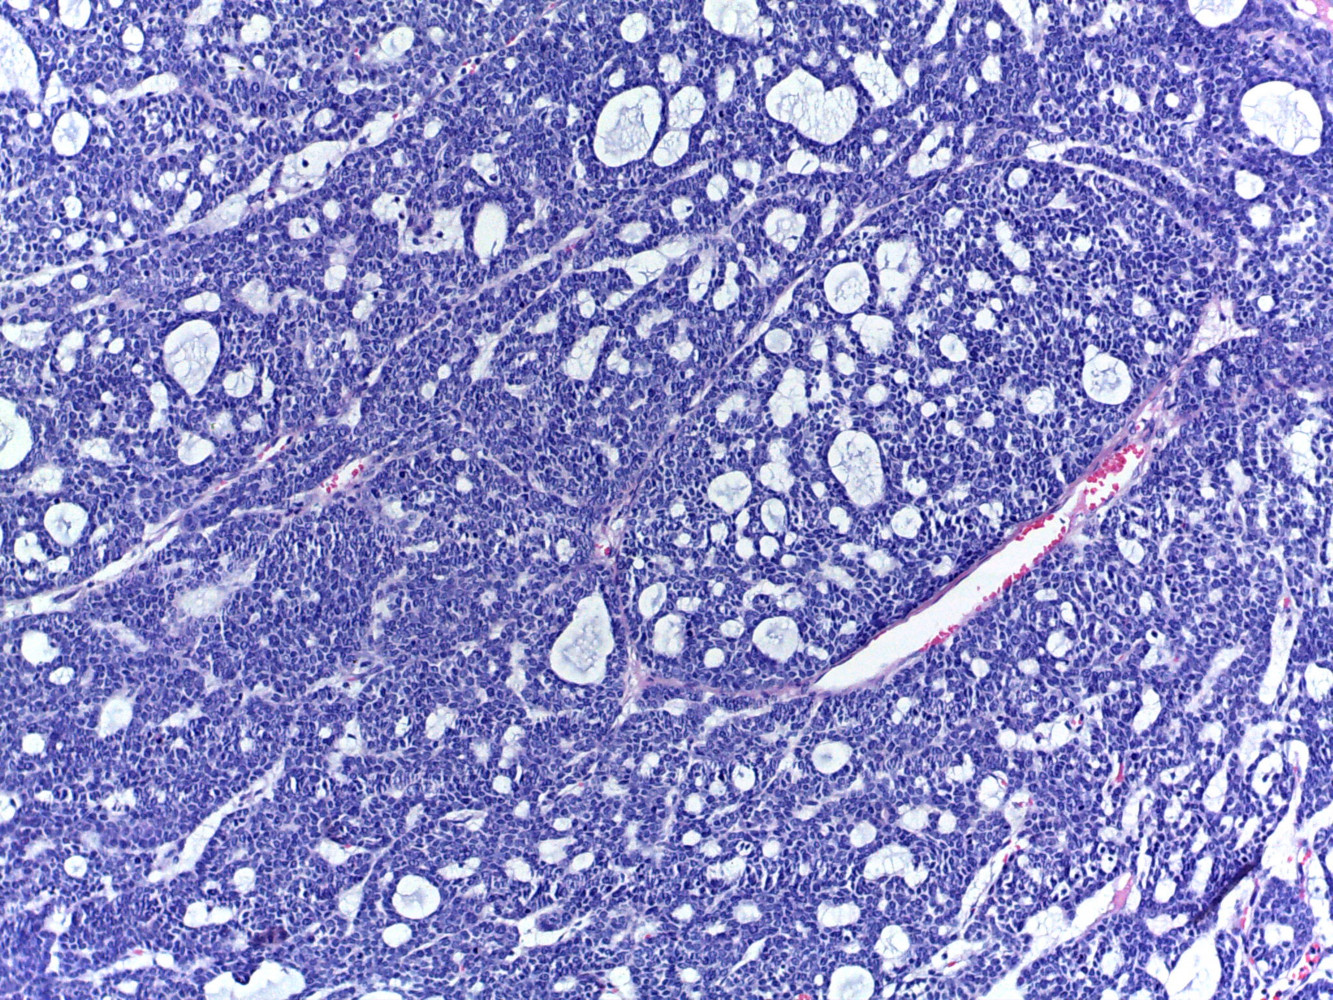

Diagnóstico: Carcinoma multifenotipico sinonasal asociado a VPH

Comentario: Anteriormente conocido como carcinoma con características semejantes al carcinoma adenoideo quístico asociado a VPH, este carcinoma se ha descrito hasta ahora solamente en tracto sinonasal, tiene características histológicas semejantes al carcinoma adenoideo quístico con componente cribiforme y tubular y un componente de carcinoma epidermoide in situ en el epitelio superficial . Todos los casos descritos están asociados a infección por VPH .